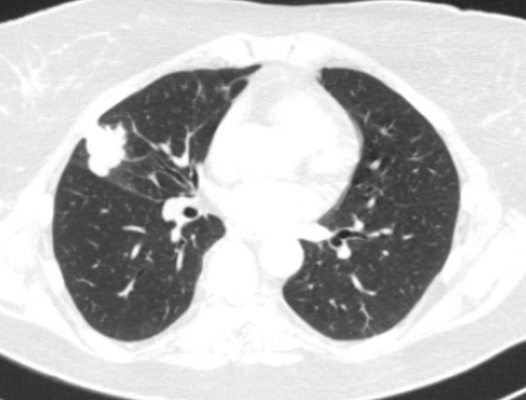

Фото 1 — Центральный рак правого нижнедолевого бронха (1) с обтурацией и метастазами (2) в бифуркационные лимфатические узлы

Периферический рак постепенно сформировывается в боковых отделах легких, медленно прорастая и ничем себя не обнаруживая. Данная опухоль легкого симптомы долгое время может не давать, они появляются при значительном местном распространении, вовлечении соседних органов и структур, прорастания бронхов. Диагностика рака легких этого типа локализации чаще всего возможна при профилактическом обследовании (рентгенографии или компьютерной томографии).

Фото 2 — Периферический рак (1) верхней доли правого легкого

Онкология легких обычно выявляется при рентгенографическом исследовании грудной клетки и компьютерно-томографическом сканировании (КТ). Диагноз подтверждается биопсией, которая обычно выполняется при трахеобронхоскопии или под КТ контролем.